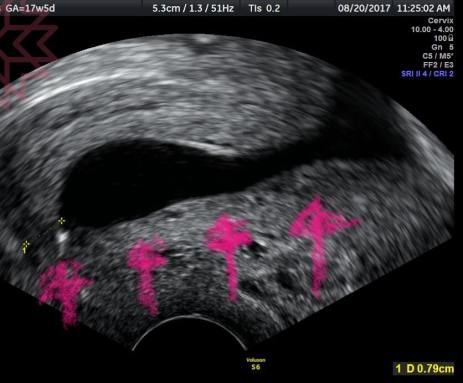

圖中箭頭所指即為原本該有的子宮頸

但因為閉鎖不全所以原本應該閉合的子宮頸內口已經張開

羊膜腔幾乎已經要突破衝出整個子宮頸

只剩最左邊一些些外口還死命撐著⋯⋯